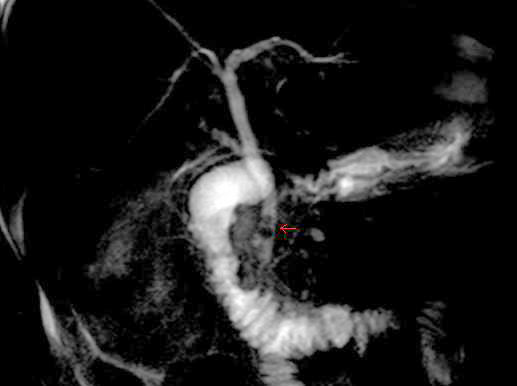

back MRCP image of two stones in the distal common bile duct